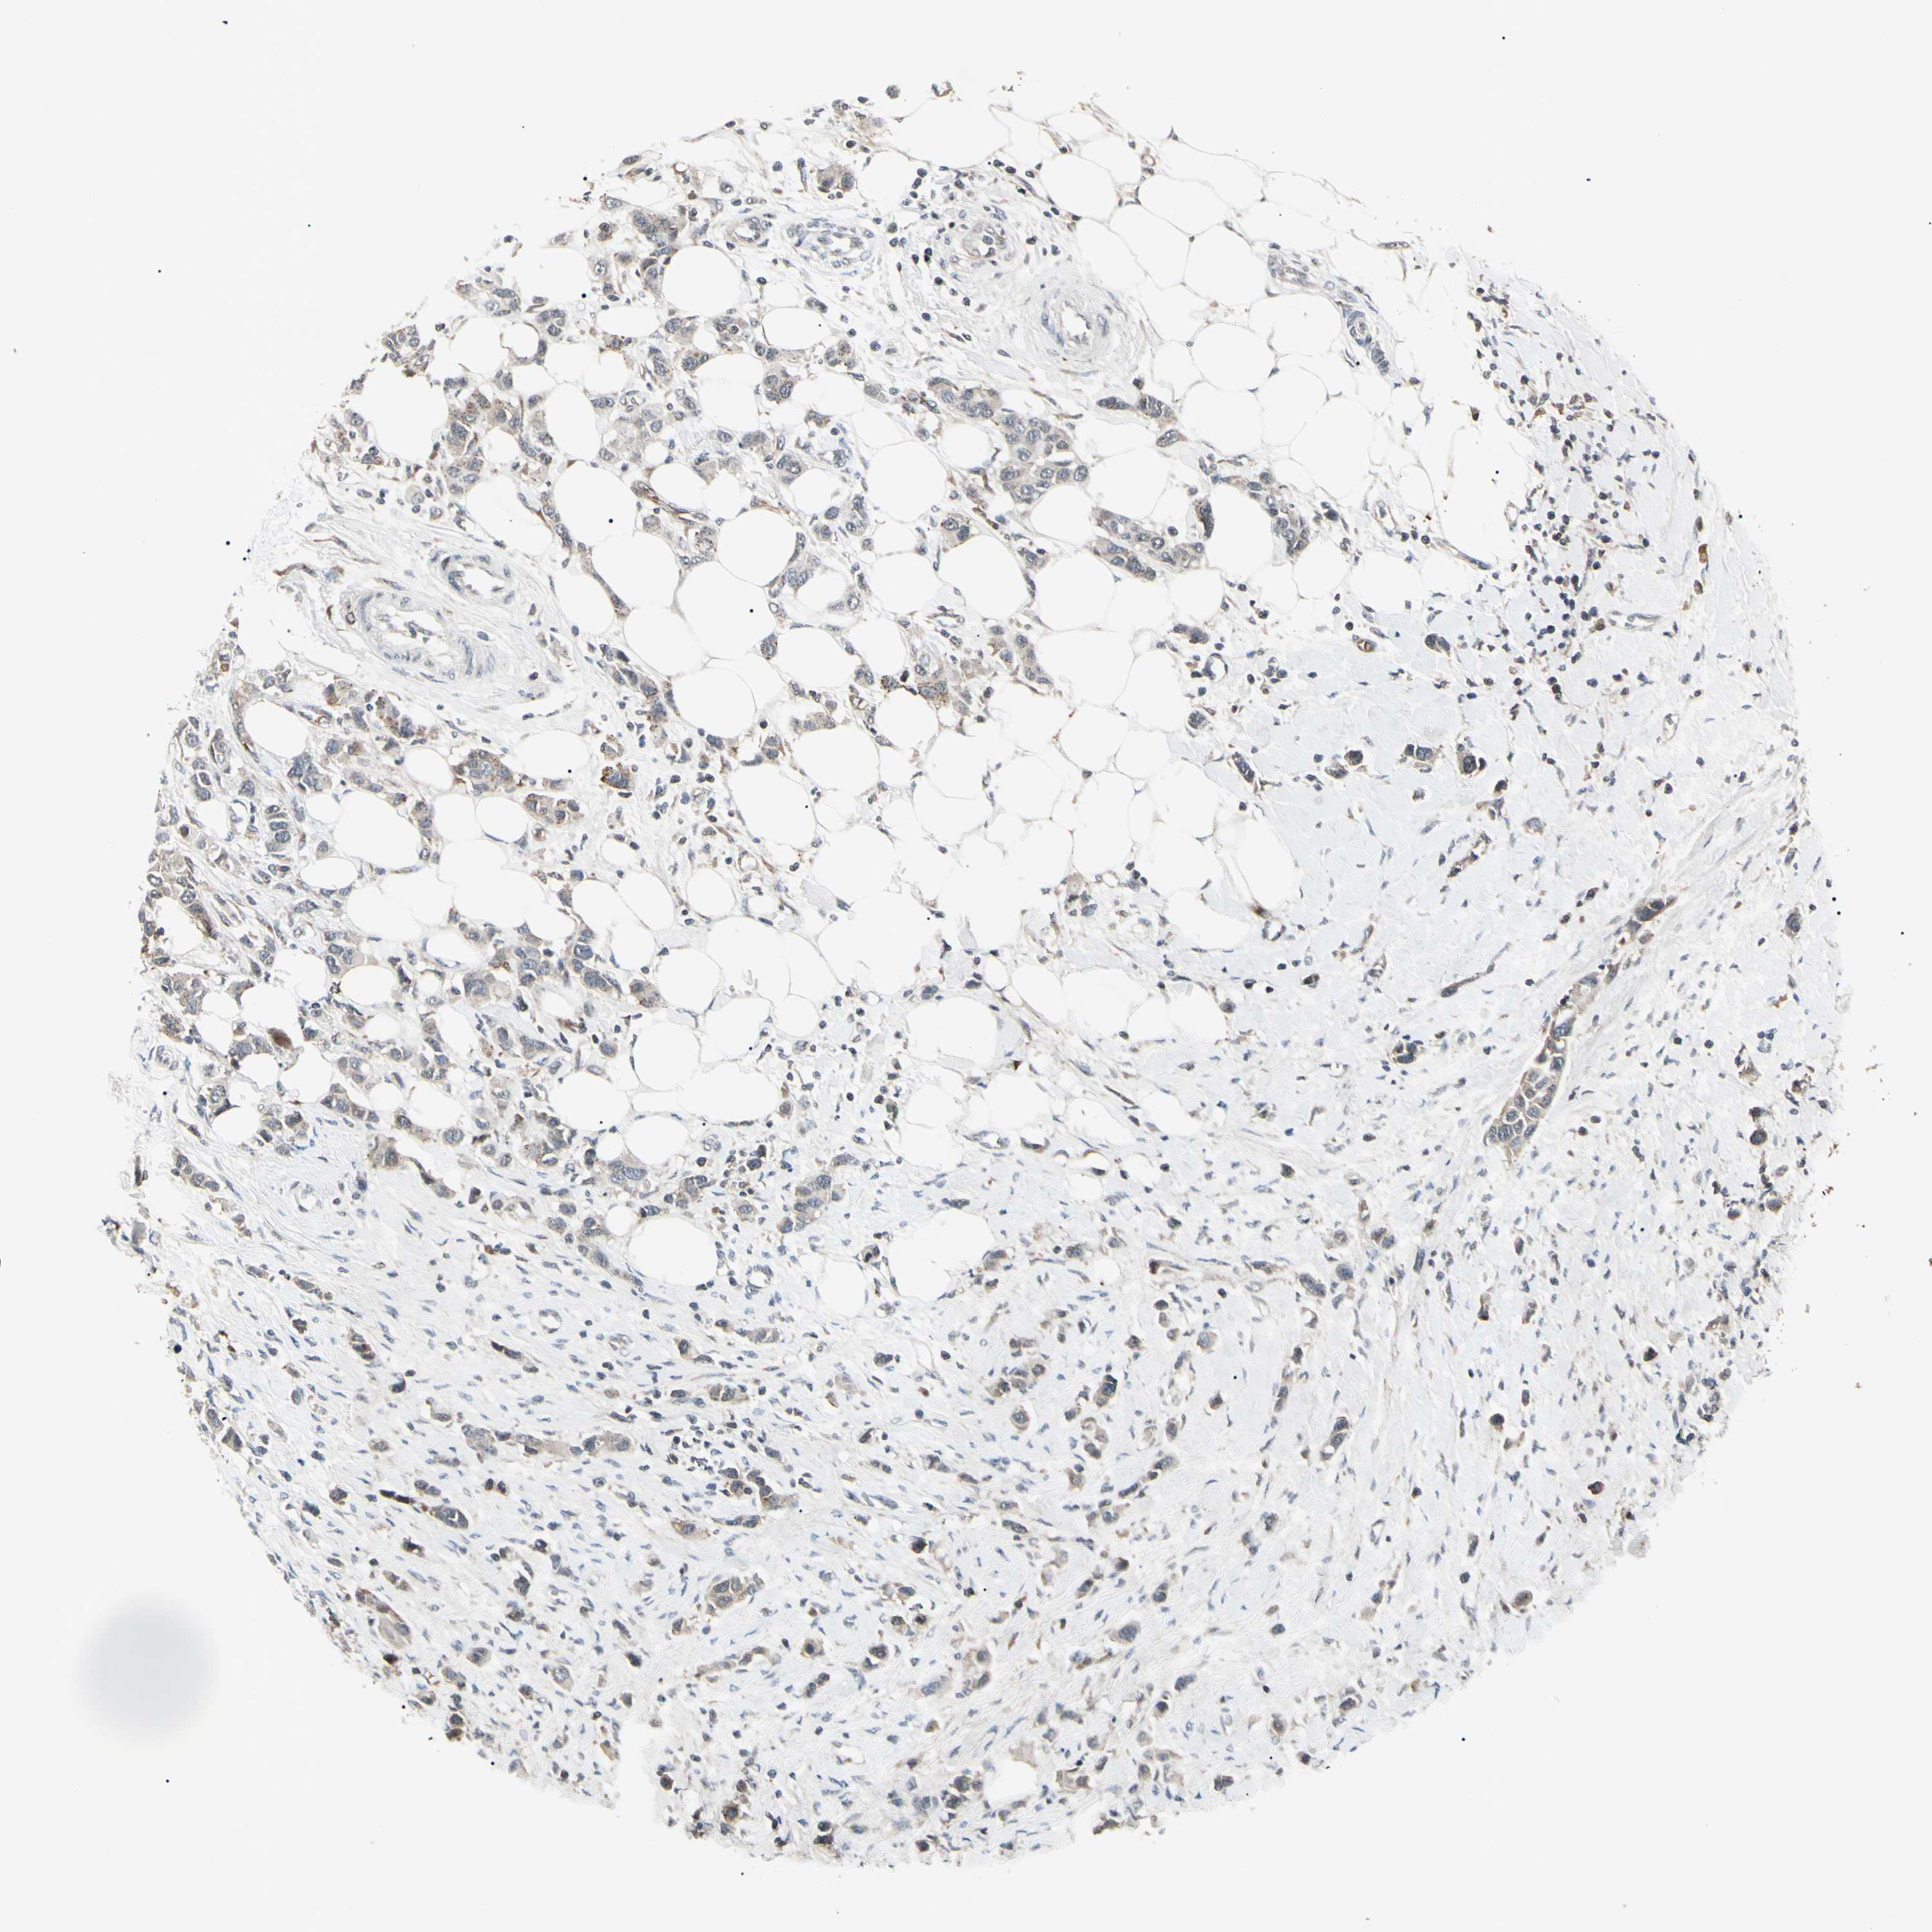

BRCA TCGA BRCA VALIDATION PROTEIN EXPRESSION